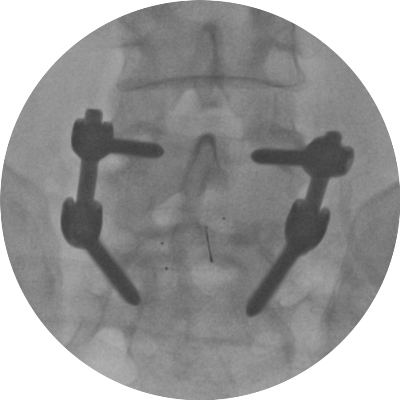

Astfel, în urma unui număr mare de investigaţii suplimentare, a fost luată decizia de a folosi un abord chirurgical numit ”fuziune intervertebrală transforaminală”. Tehnica dată este mai complicată şi mai solicitantă faţă de dotarea tehnică a blocului de operaţii şi a abilităţilor echipei chirurgicale, însă oferă un şir de avantaje pentru pacient.

Deoarece pacientul a fost operat anterior de 2 ori, utilizarea aceluiaşi coridor chirurgical tradiţional putea fi însoţită de un risc mare de leziuni a nervilor şi vaselor în canalul spinal. De aceea, a fost aleasă o cale mai puţin utilizată în practica cotidiană, dar care a fost cea mai raţională pentru pacientul dat, aşa-numitul abord paramedian transmuscular sau abordul prin spaţiul Wiltse.

Este un caz fericit pentru pacientul din Italia şi de succes pentru secţia Neurochirurgie, dar şi pentru întreaga instituţie medicală, or, astfel de intervenţii complicate au devenit posibile în Republica Moldova în urma deschiderii noului Bloc chirurgical în luna mai curent, prin intermediul căruia ţara noastră a obţinut facilităţi şi posibilităţi care au existat pînă nu demult doar în centrele medicale contemporane performante din lume. Astfel, sala de operaţii Hybrid a blocului dispune de metode de neuroimagistică intraoperatorie şi sisteme de monitoring şi neuronavigaţie, sisteme specializate de implanturi din titan şi instrumente chirurgicale, echipamente pentru disecţie osoasă. Acest complex chirurgical este completat de un departament ultradotat de anestezie şi neuroreanimare, care asigură o parcurgere perioperatorie fără complicaţii.